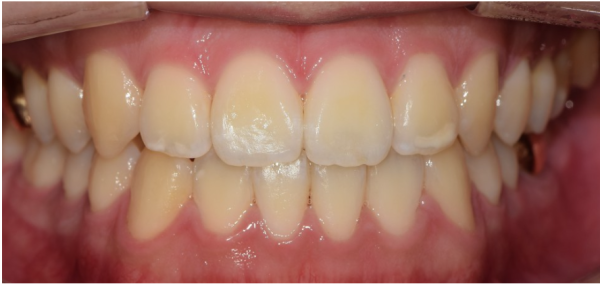

이 환자분의 치아 사진입니다.

정면에서 보았을대 치아가 정상적으로 겹치는게 아니라

맞 닿아 있습니다.' 이러한 치아를 엣지 투 엣지(edge to edge)라고 합니다.

This is a picture of your teeth.

He saw it from the front. His teeth didn't overlap normally

It's touching.' These teeth are called edge to edge.